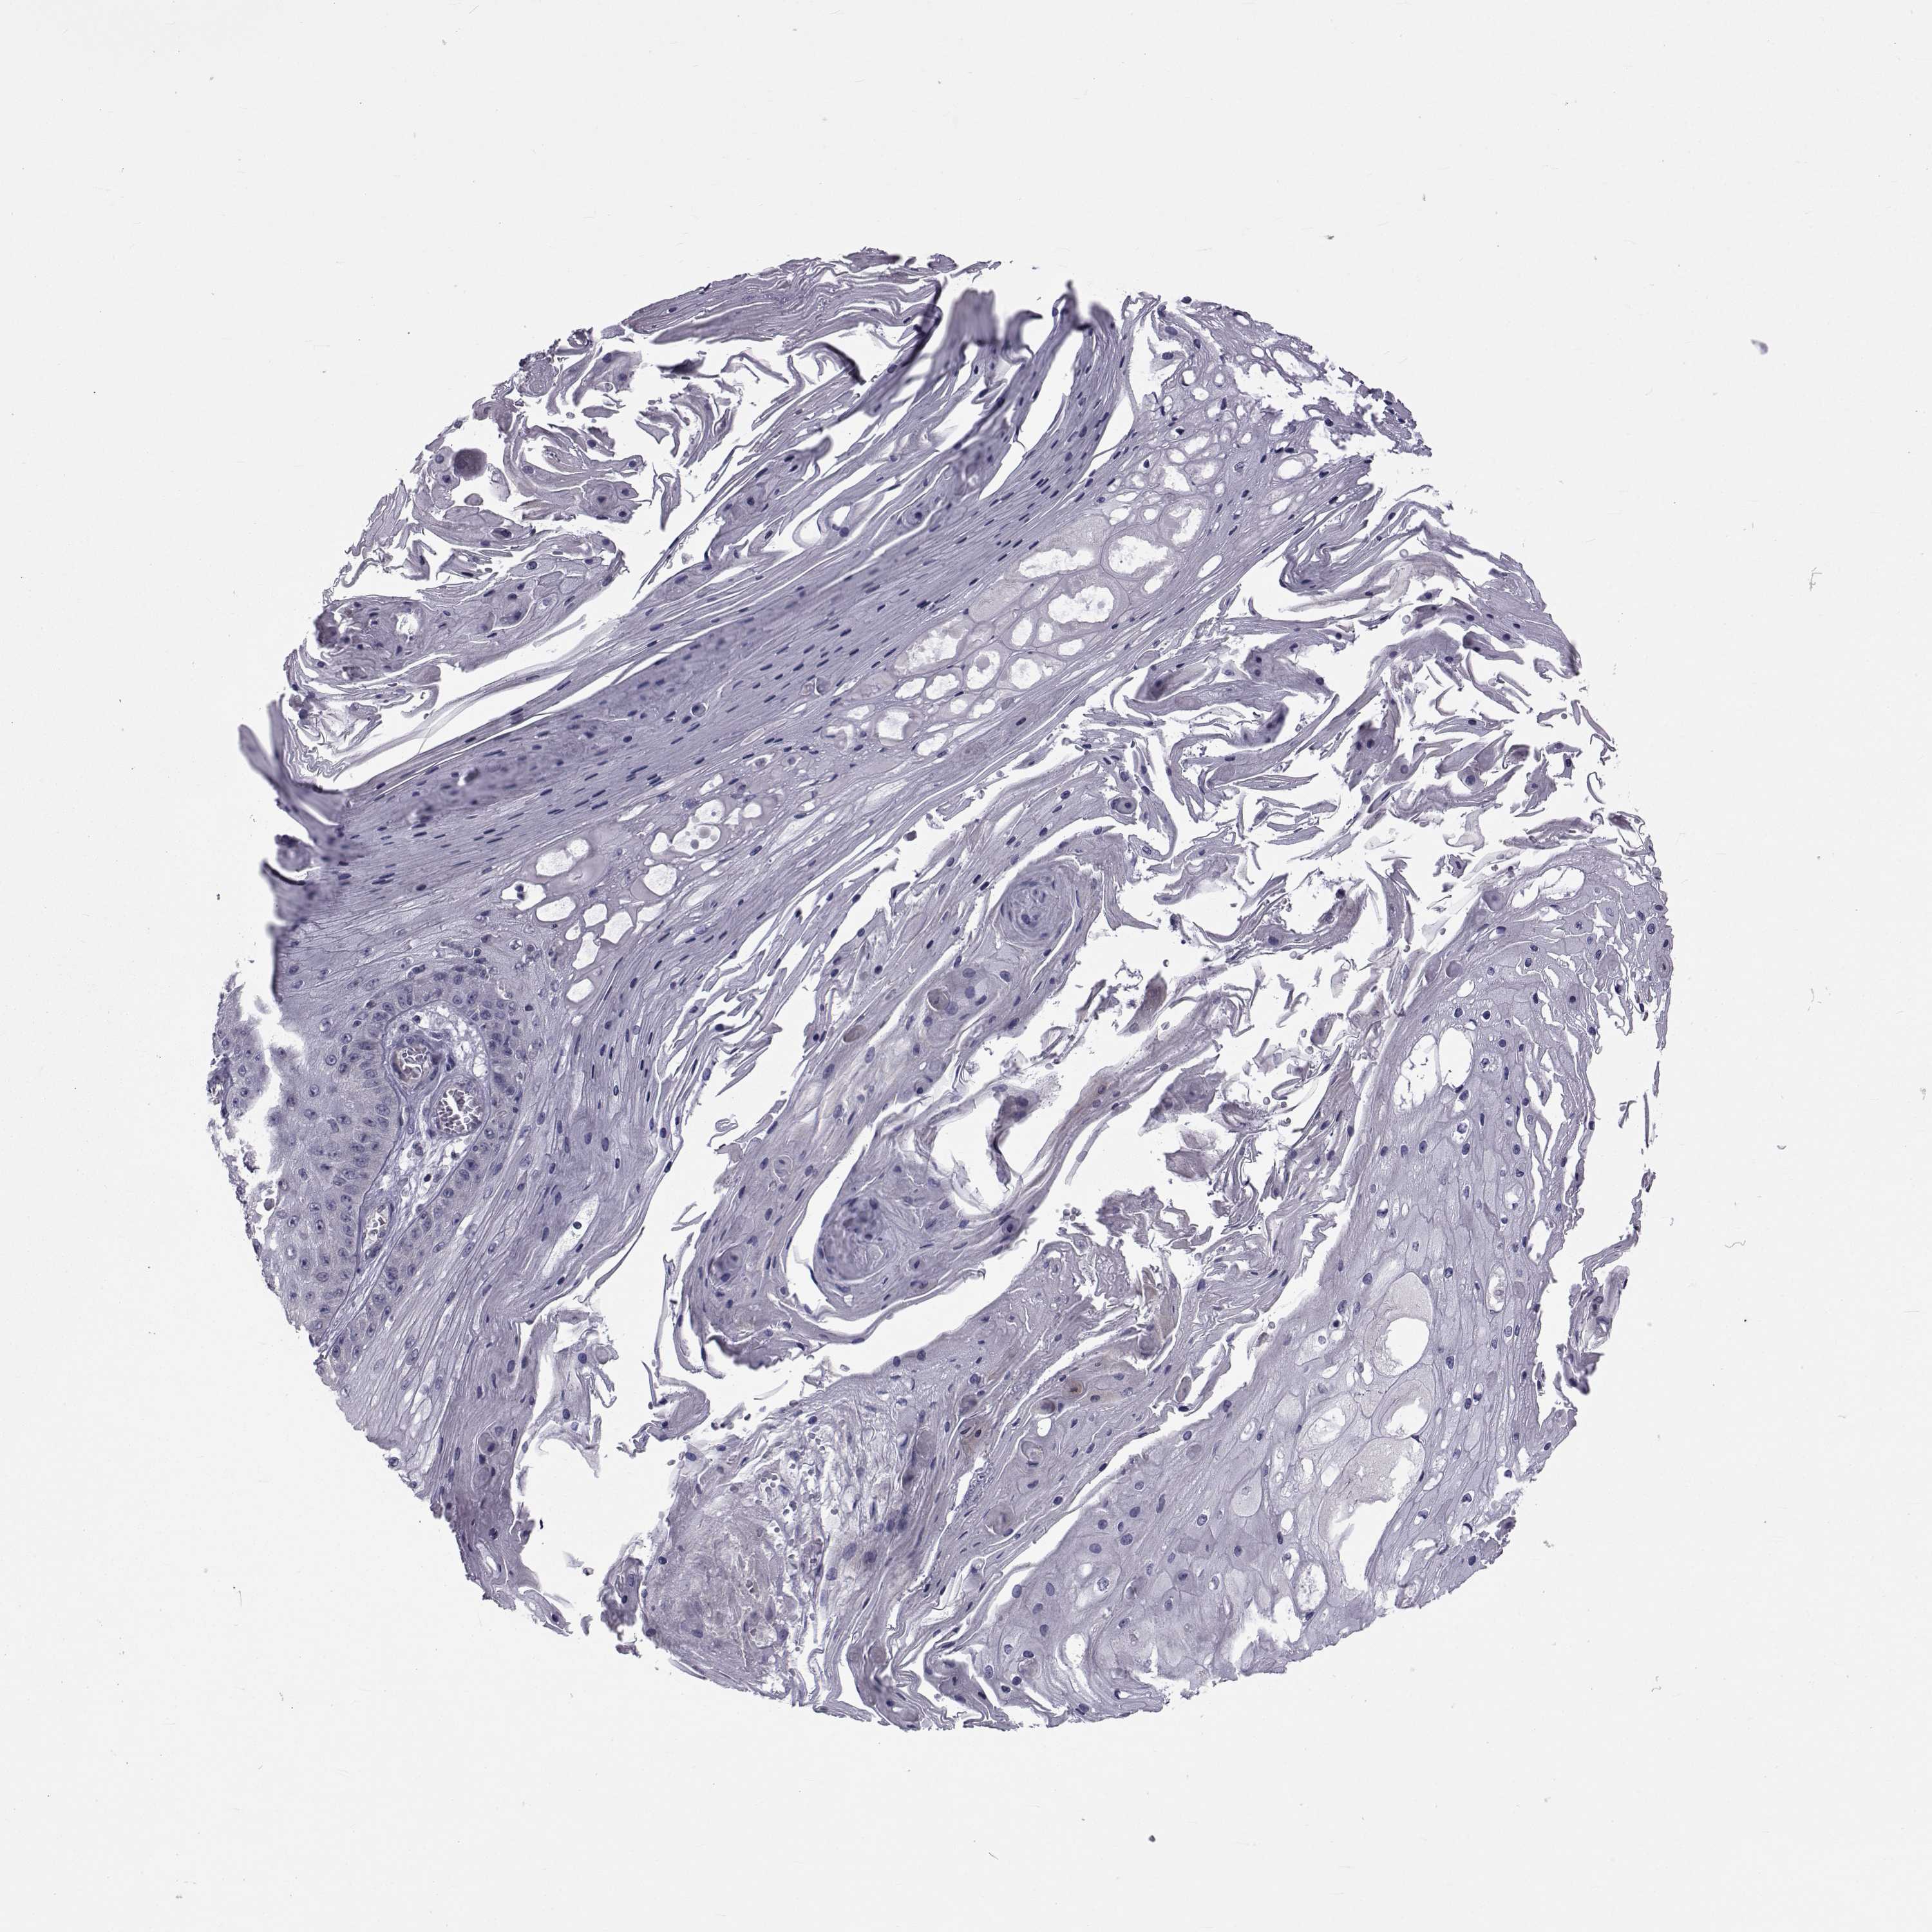

CANCER SKIN CANCER Show tissue menu

SKIN CANCER - Protein expressioni

A mouse-over function shows sample information and annotation data. Click on an image to view it in a full screen mode. Samples can be filtered based on level of antibody staining by selecting one or several of the following categories: high, medium, low and not detected. The assay and annotation is described here.

Each image is clickable and will lead to virtual microscopy that enables deeper exploration of all samples and also displays staining intensity scores, fraction scores and subcellular localization as well as patient and tissue information for each sample.

Antibody HPA028521

Antibody HPA029274

Antibody HPA030240

Squamous cell carcinoma, NOS